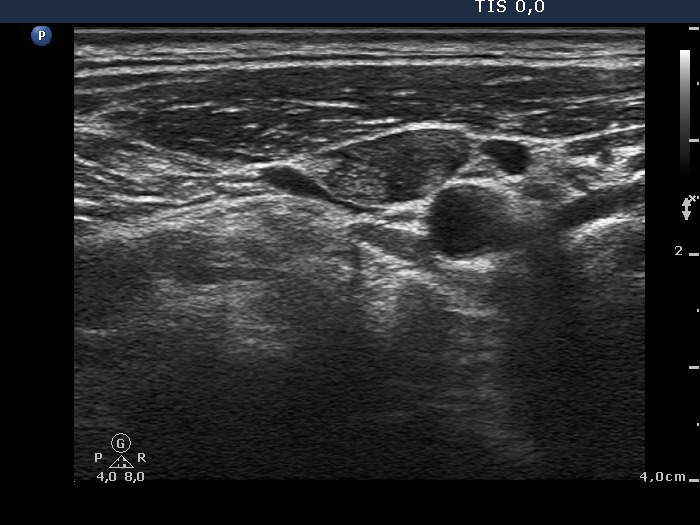

Thyroid cancers - case 678 (ultrasonographic picture 7)

Right side of the neck, transverse scan. There is an enlarged lymph node ventral to the artery carotid. There is a hyperechogenic area in the lateral part of the lymph node.